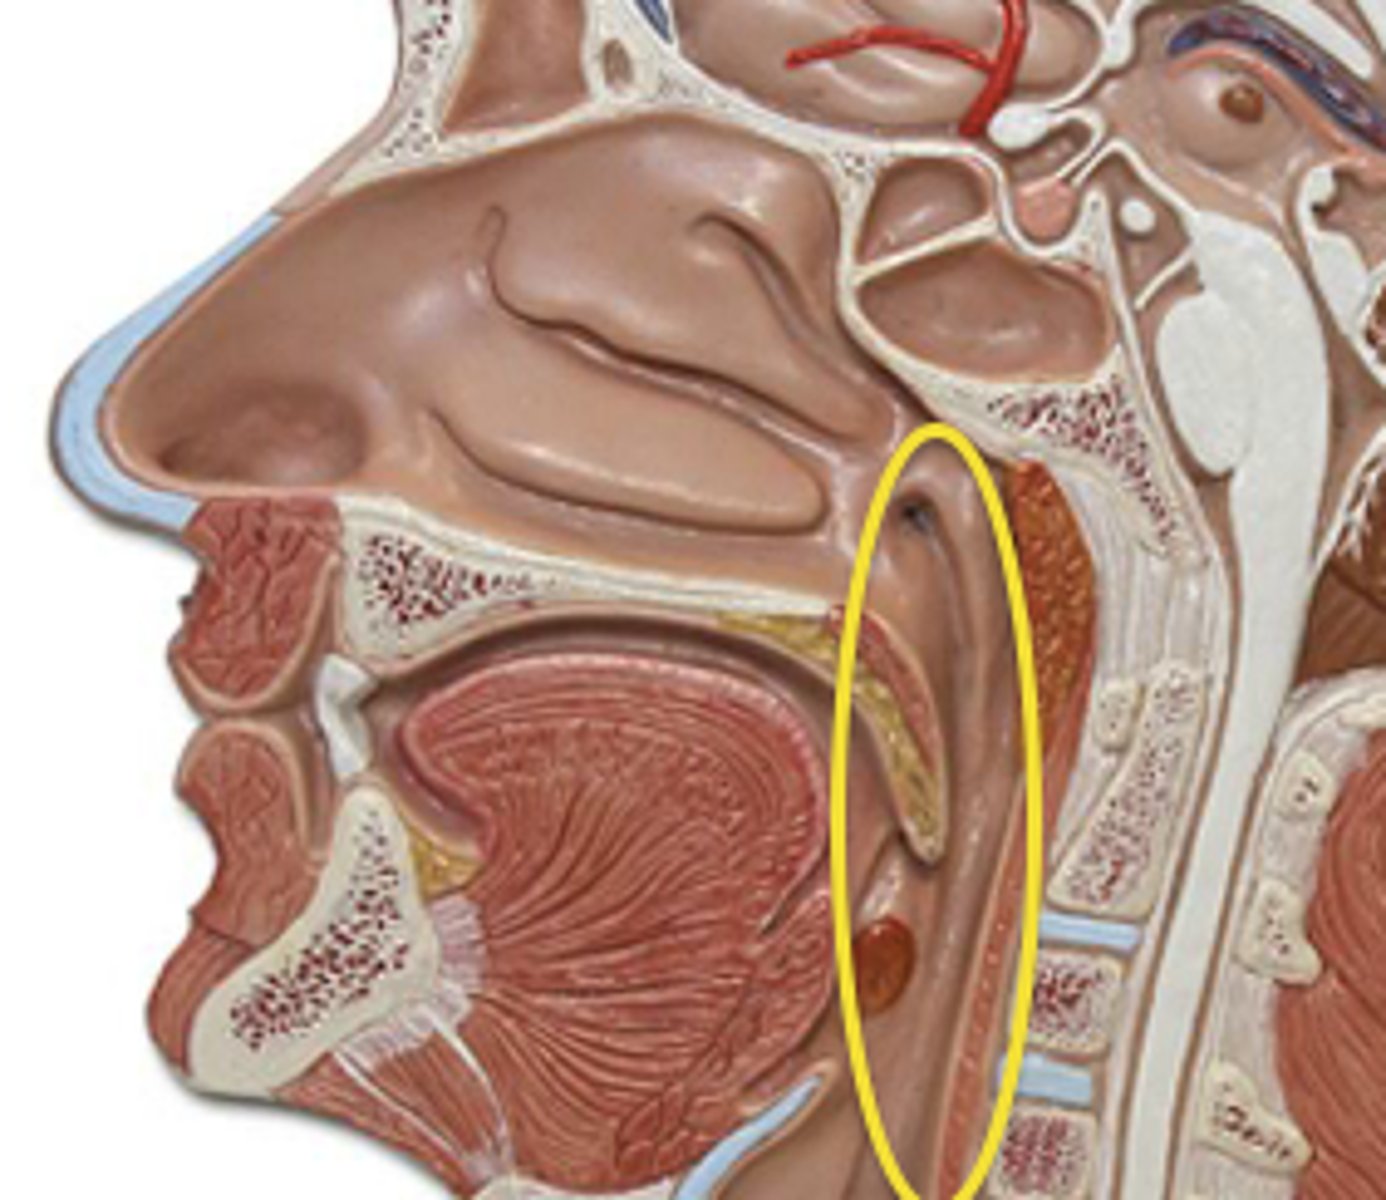

Pharynx

oropharynx

Epiglottis

laryngopharynx